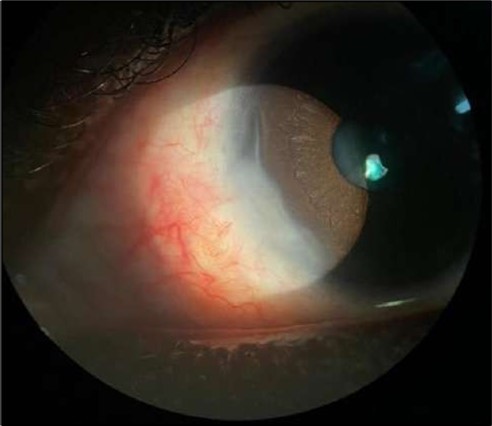

On the current presentation, Snellen VA was 6/6 in the right eye and 6/9 in the left eye, with normal IOP. The left eye demonstrated mild upper lid edema and intense nasal ciliary injection. Slit-lamp evaluation revealed a crescentic area of stromal corneal melting between 7 and 10 o’clock nasally, with overhanging edges and a fluorescein-positive base. No corneal infiltrates were present, and the surrounding stroma remained clear. The anterior chamber was deep and quiet, lens was transparent, pupil was round and reactive & normal posterior segment. Anterior segment optical coherence tomography (AS-OCT) confirmed a localized ulcer, measuring 1324 µm in horizontal width and extending to a depth of 380 μm, compared with an adjacent healthy corneal thickness of 824 µm, corresponding to approximately 46.1% stromal thinning (Figure 1a, Figure 1b, Figure 1c)

Figure 1a.Left eye (OS), on presentation. Slit-lamp image: crescent-shaped peripheral corneal ulceration located nasally, with severe adjacent conjunctival injection, peripheral thinning, and stromal infiltration.

Left eye (OS), on presentation. Slit-lamp image: crescent-shaped peripheral corneal ulceration located nasally, with severe adjacent conjunctival injection, peripheral thinning, and stromal infiltration.

Despite systemic and topical management over one month, the epithelial defect persisted, indicating refractoriness to medical therapy. OCT imaging showed ulcer depth reduction to nearly 42% stromal thinning and width of 1180 µm, highlighting partial corneal healing. In view of the persistent ulcer and ongoing local inflammation, a conjunctival resection was performed to excise the perilimbal inflammatory focus and promote corneal repair Figure 3a and 3b.

Figure 3a and 3b.OS, Intraoperative photo showing excision of a 4 mm-wide strip of perilimbal conjunctiva between 7 and 10 o’clock, adjacent to the area of stromal ulceration.

OS, Intraoperative photo showing excision of a 4 mm-wide strip of perilimbal conjunctiva between 7 and 10 o’clock, adjacent to the area of stromal ulceration.